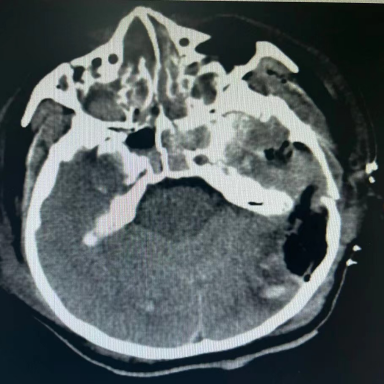

积极抢救后,王先生的血压终于有所上升,立刻为他进行头颅+胸部+全腹部 CT,检查结果显示:他的双侧额骨、颞骨、蝶骨骨折,颅底骨折,颅内积气,左侧颞顶部及右侧顶枕部硬膜下血肿、蛛网膜下腔出血,颈椎 567 锥体横突骨折,右 6-9 肋骨多根多处骨折伴有肺挫伤。

经过 2 个小时紧张的综合抢救后,王先生的血压明显改善,生命体征逐渐稳定,复查头颅 CT,检查结果显示,脑出血明显增多伴有中线偏移,脑疝形成。

ICU 与神经外科沟通后,紧急为王先生进行去骨瓣减压+血肿清除术。手术进行得很顺利,术后王先生转回 ICU 继续抢救治疗。